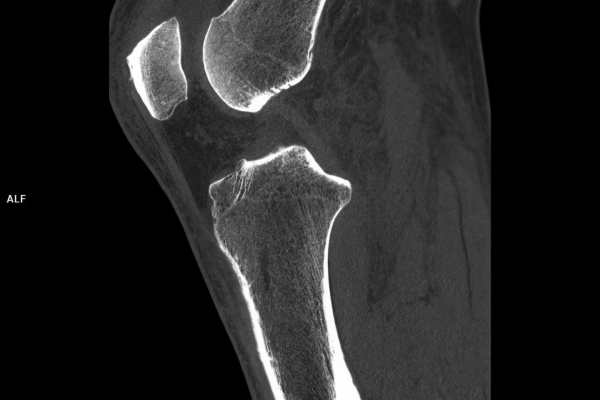

CT Untersuchung Bild

Wir verbinden modernste Medizin mit einer Atmosphäre, in der Sie sich sicher und gut aufgehoben fühlen. Klare Abläufe, Ruhe und Zeit für Sie stehen im Mittelpunkt jeder Untersuchung. CT- und MRT-Bilder ohne Wartezeit. Mit Photon-Counting-CT und 3-Tesla-MRT setzen wir auf in Kärnten einzigartige Technologien für außergewöhnlich detailreiche Bilder und besonders präzise Diagnosen. Die schonenden Verfahren eignen sich auch für Kinder und Jugendliche. Kurze Messzeiten, große offene Geräte und ein ruhiges Umfeld sorgen für eine angenehme Untersuchung und ein gutes Gefühl von Anfang bis Ende.

Die MRT (Magnetresonanztomographie) arbeitet mit Magnetfeldern und Radiowellen und eignet sich besonders für Untersuchungen der Weichteile wie Gehirn, Muskeln oder Gelenke. Die CT (Computertomographie) nutzt Röntgenstrahlen und liefert schnelle, hochauflösende Bilder, insbesondere für Knochen, Lunge oder innere Organe. Die Wahl der jeweiligen Untersuchung richtet sich an das individuelle Krankheitsbild und wird bei der Überweisung festgelegt.